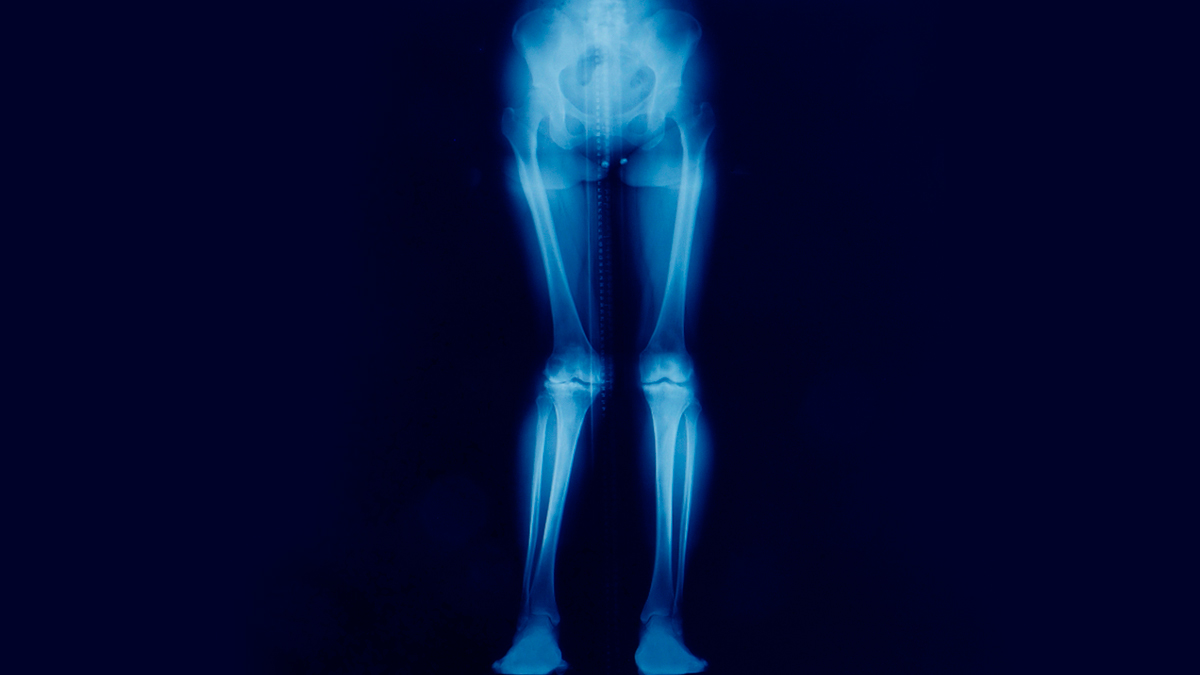

Our feet are the foundation for the alignment of our bodies. Whenever the shoes don't support the feet properly, or force unnatural positions onto your feet, it can trigger a chain reaction all the way up the legs to knees, hips, and even lower back. "When the foot is not well-supported, the body tries to compensate by altering posture and gait. Over time, this puts extra stress on the hips, leading to pain and stiffness," Dr Jayateerth explained.

Shoes that are too tight, too flat, or too high will affect how your body weight is distributed. For example, high heels throw the body's weight forward, tilting the pelvis and overworking the hip muscles. Likewise, very flat shoes or flip-flops with no arch support will make the feet roll inward, disrupting hip alignment and leading to hip joint pain.